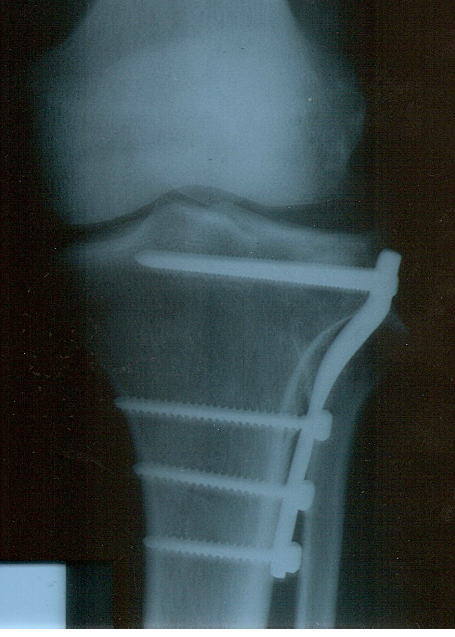

tzitzikas 0 Report post Posted September 12, 2009 (edited) παιδια καλησπέρα. ¨Εχω αυτο που ειναι στην παρακάτω φωτο. Απο κάταγμα εξω κνημιαίου κονδύλου τύπου ΙΙ. Κανεις με παρόμιο πρόβλημα μετά απο πόσο καιρό το έβγαλε? Μελλοντικά ειχε καποιος πρόβλημα? Ειναι απαραίτητο να βγεί? Το έχω 1 χρόνο και 2 μήνες. Απο μηχανακι ειναι. Η μαγνητική είχε δειξει και ρωγμη στο μηνίσκο κατηγορίας ΙΙ. Αυτο πρεπει να το δω περαιτέρω? Edited September 12, 2009 by tzitzikas Quote Share this post Link to post Share on other sites